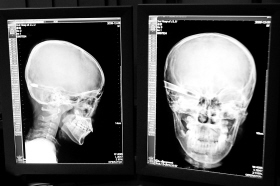

在接受x光檢查的小沖

“還是先做個(gè)X光透視,看一下箭桿到底有多深!毖劭漆t(yī)生緊急趕到CT室查看,和放射科的幾位醫(yī)生共同研究后,決定先讓小沖做X光透視。

“如果再用點(diǎn)力,就從后腦穿出來(lái)了!”由于小沖無(wú)法移動(dòng),醫(yī)生拿來(lái)移動(dòng)插座,將透視的光板放在小沖的移動(dòng)病床上,透視后讓在場(chǎng)的醫(yī)生都吃了一驚:箭桿直接穿過了大腦和小腦,箭尖兒直抵后顱骨,足足有10余厘米。